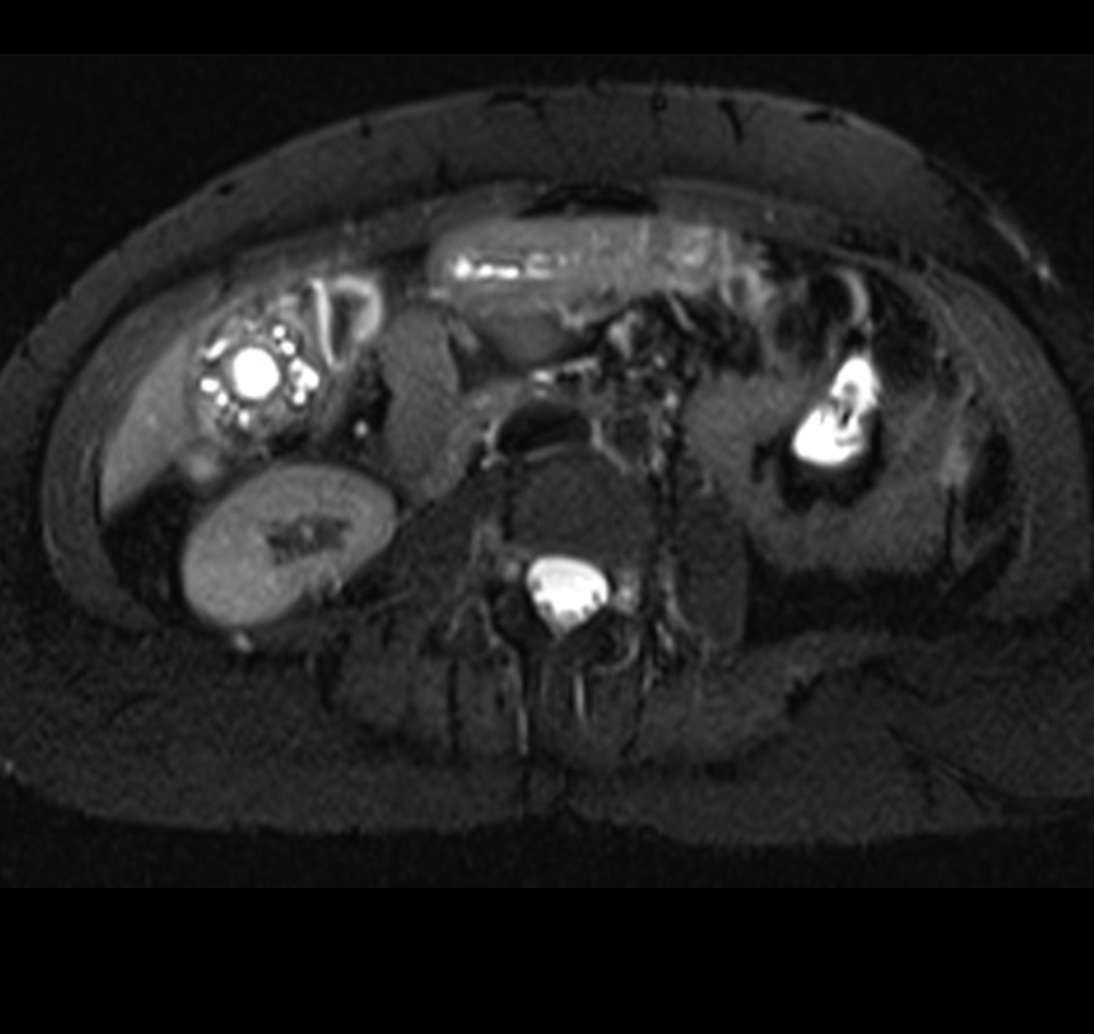

what is this?

Biliary cystadenoma

- uncommon, multilocular cystic liver mass that originates in the bile duct and usually occurs in the right hepatic lobe.

- Typically occurs in women

- h/o chronic abdominal pain

- it may represent a congenital anomaly of the biliary anlage

- COMPLICATIONS

- Malignant transformation cystadenocarcinoma occurs

- IMAGING FEATURES

- well defined and cystic

- internal sepations

- The cyst walls and any other soft tissue components typically enhance with contrast

- variable appearance on MRI depending on the protein content of the fluid and the presence of an intracystic soft tissue component.